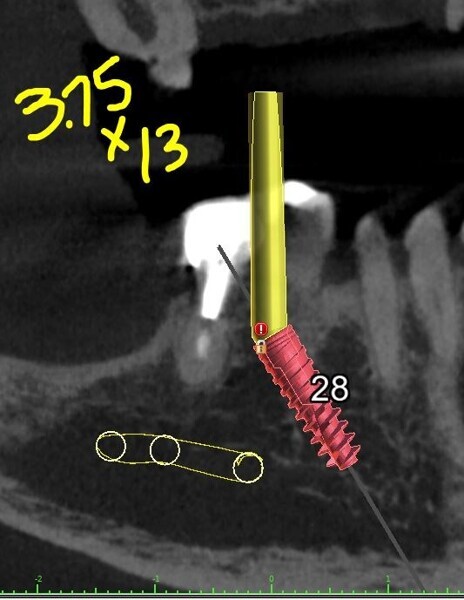

Each potential implant receptor site was designated by tooth number for the maxillary and mandibular arches. Manufacturer-specific simulated implants were then refined within the cross-sectional images, recording diameters and lengths in screenshots for the maxilla (Fig. 4) and the mandible (Fig. 5) utilised during the surgery as colour printouts.

Figs. 5a–e: Implant planning for the mandibular arch with straight and angled multi-unit abutments.